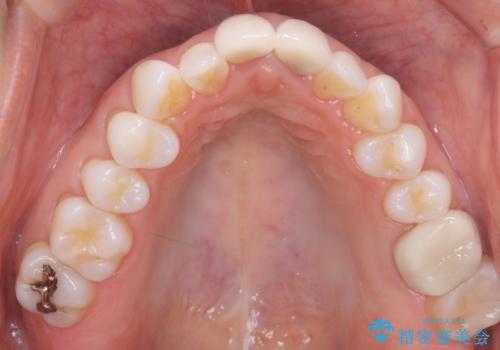

- メンテナンスでいらっしゃった患者様です。

歯を保護するためのナイトガードを装着していきます。